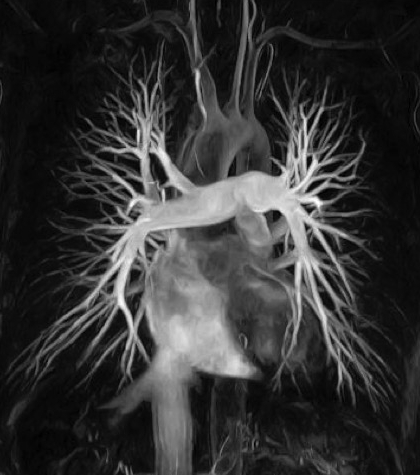

La hipertensión pulmonar es una condición en la que la presión arterial en las arterias de los pulmones (las arterias pulmonares) está anormalmente elevada. A medida que aumenta la presión, el ventrículo derecho de su corazón tiene que trabajar más duro para bombear sangre a través de sus pulmones. Esto eventualmente hace que su músculo cardíaco se debilite y eventualmente falla completamente.

Otro tipo de HP, llamada hipertensión pulmonar secundaria, ocurre cuando las arterias de los pulmones se vuelven demasiado estrechas para que la sangre fluya de forma normal a través de los vasos o porque hay muy pocos vasos desde el inicio. La estrechez de los vasos en la hipertensión secundaria puede ser causada por una afección médica asociada como coágulos de sangre, defectos congénitos del corazón y enfermedad hepática.